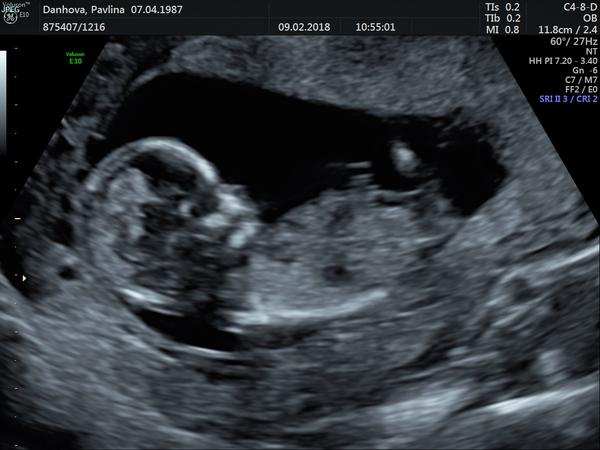

Ahoj 🙂 momentálně jsem ve 14tt. Ve 12+4tt jsem byla na screeningu v Ústí a zeptala jsem se, jestli jde už poznat nějaké pohlaví. Doktorka se na mě podívala a řekla mi, jestli si to přejeme vědět, ze je to za poplatek s 95% přesností. Tak jsem kývla a doktorka hned řekla, ze podle pohlavního hrbolku to vypadá na holcicku :D ukazala nám, jak by to vypadalo, kdyby to byl kluk a vše nám popsala. Ale já stejně stále přemýšlím a zkoumam fotku...Mimochodem každý kdo na tehle klinice byl, tak jim to pohlaví sdělili a opravdu to tak bylo. Tak co myslíte 🙂)

Tak pry to vypadá na holku...

@2hanah Je tam vidět jen pohlavní hrbolek 🙂. Pohlavi se určuje podle jeho sklonu. Když směřuje nahoru, tak kluk, když rovnoběžně se zakřivením páteře, tak holka. Na velký ultrazvuk jdu az za 2 týdny 🙂. Ovšem zatím většina tipovala holcicku... Sama jsem zvědavá, co to je... Na druhou stranu přemýšlím, jestli si nenechat překvapeni do porodu 🙂